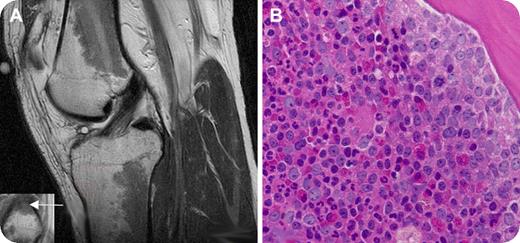

Laboratory tests showed a white blood cell count of 25.3 × 109/L with 55% neutrophils, 8% bands, 5% myelocytes, 6% metamyelocytes, 21% lymphocytes, 4% monocytes, and 1% basophils; hematocrit of 43.7%; and platelet count of 203 × 109/L. A bone marrow aspirate and biopsy from the left posterior-superior iliac crest revealed hypercellularity with granulocytic predominance (panel B). Karyotypic analysis revealed a Philadelphia chromosome (t (9;22)). The patient was diagnosed with chronic myelogenous leukemia (CML) and therapy with imatinib mesylate was initiated.

The abnormalities on the MRI scan, when viewed in the absence of known hematologic abnormalities, were initially attributed to red marrow reconversion, which may be secondary to athletic activity. However, similar findings can indeed be seen in myeloproliferative disorders and marrow replacement disorders. Clinicians should be aware of unusual presentations of hematologic disorders in seemingly healthy patients with abnormal bone marrow signal on MRI scans.